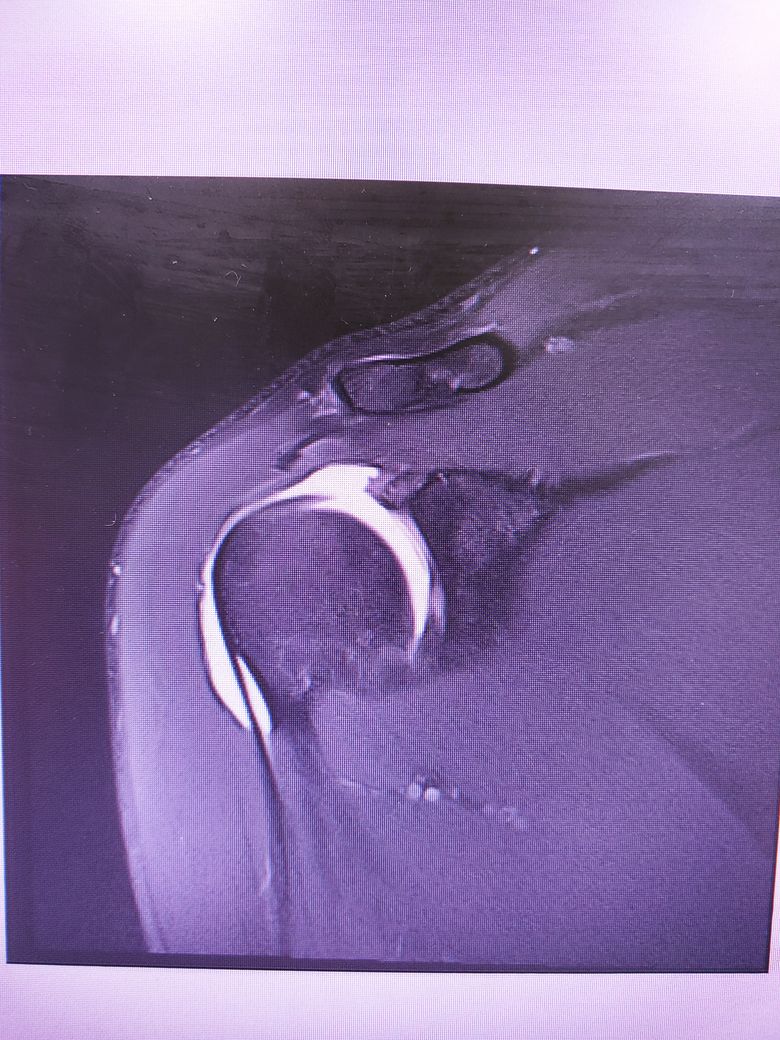

팔이 잡아당겨지는 사고 이후 통증이 지속되어

조영제 투입 후 mri 촬영을 하였습니다.

진단명은 상부관절와순파열(슬랩)이며

헬스와 같은 운동을 계속 하려면 수술이 필요하다 하였습니다.

슬랩이 맞나요? 맞다면 파열 진행 정도는 어느정도인지..

궁금합니다..최대한 사진 많이 올립니다 감사합니다..